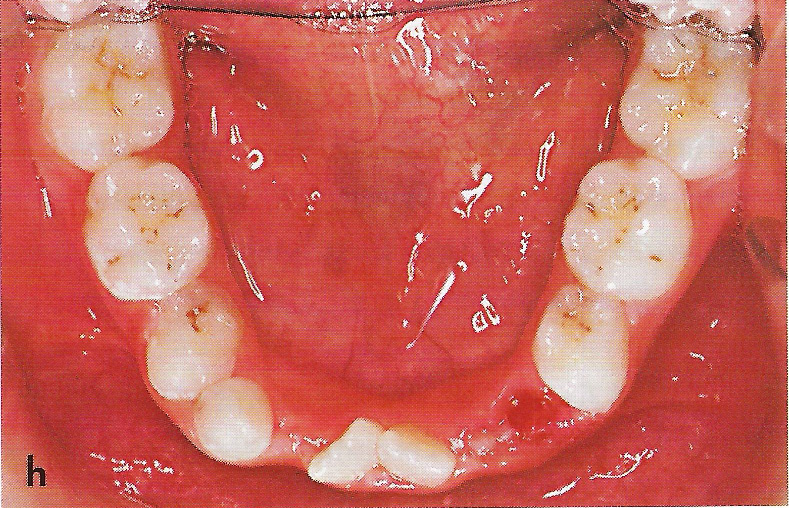

Abb. 1 a bis h Extra- und intraorale Ansicht der Patientin vor Behandlungsbeginn: Kopfbiß beziehungsweise umgekehrter Schneidezahnüberbiß und beidseitiger Kreuzbiß als Folge einer maxillären Hypoplasie sowie hälftenungleicher Mesialbiß infolge mandibulärer Verschiebung nach rechts.

• Ankylose Abb.1h

Diese Patientin war zu Behandlungsbeginn 7 Jahre alt. Sie hatte einen hälftenungleichen Mesialbiß infolge mandibulärer Verschiebung mit Kopfbiß beziehungsweise umgekehrter inzisaler Stufe, rechtsseitigem vollem Kreuzbiß und linksseitigem doppeltem Höckerbiß, maxillärer Kompression sowie Platzmangel in beiden Kiefern (Abb. 1 a bis h). Die kephalometrische Analyse ergab eine progene Kieferlagebeziehung, bedingt durch eine unterentwickelte Maxilla bei vertikalem Gesichtsschädelaufbau.